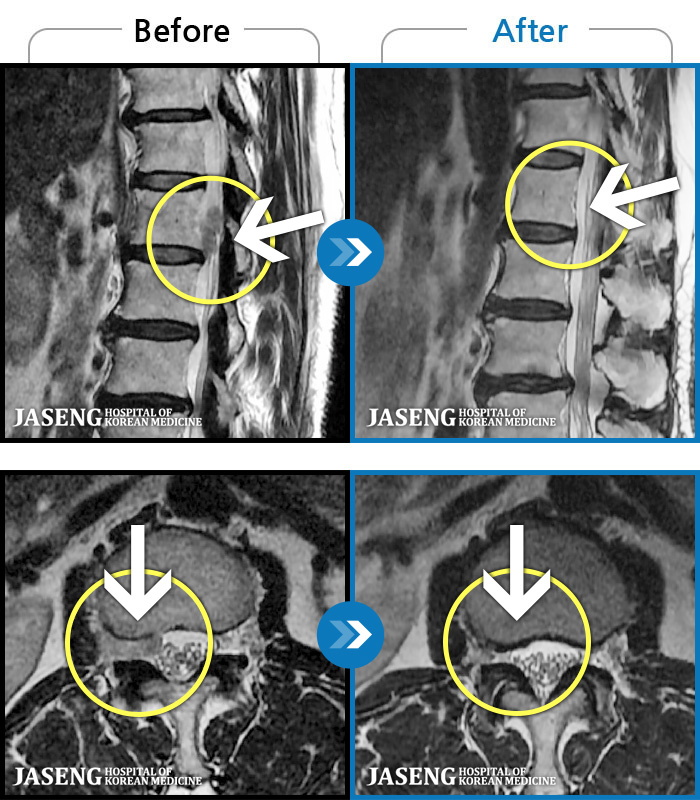

ȯںп Ǹ ǿ ԿǾ, ο ġ ۿ Ƿ ġḦ Ͻñ ٶϴ.